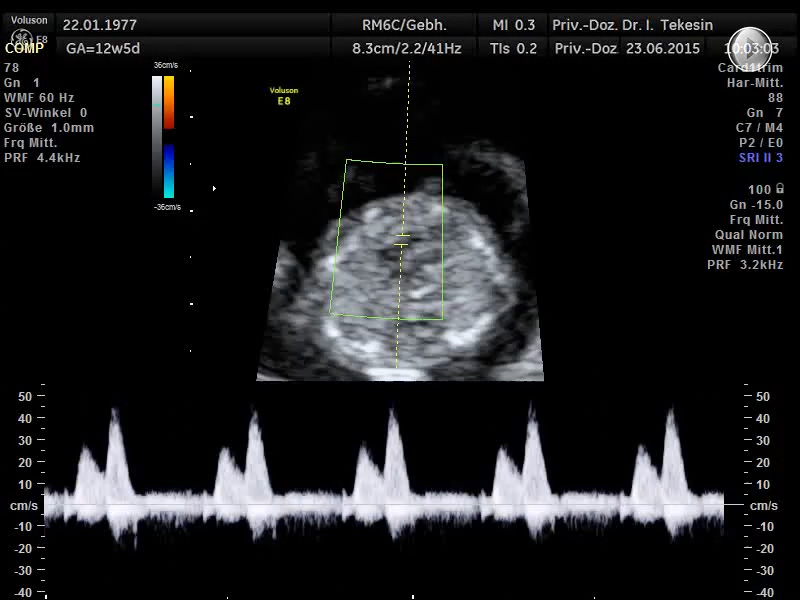

Ein weiterer Bestandteil der weiterführenden Ultraschall-Diagnostik ist die Beurteilung des kindlichen Herzens und der großen Blutgefäße, die fetale Echokardiographie. Dabei untersuchen wir die Lage, Größe und Symmetrie des Herzens, Anatomie der Herzstrukturen, Funktion der Herzklappen, Herzfrequenz und die Lage der großen Gefäße. Mit Hilfe der farbkodierten Doppler-Sonographie des Herzens werden weitere Details untersucht: die Funktion der Herzkammern, Herzscheidewände, Blutflüsse im Herzen und Blutflüsse in den großen Gefäßen.

Das Ziel dieser Ultraschalluntersuchung des fetalen Herzens ist der weitest mögliche Ausschluss von angeborenen Herzfehlern. Die Voraussetzung hierfür sind eine spezielle Ausbildung und Erfahrung des Arztes in Verbindung mit der hohen Qualität des Ultraschallgerätes.

Dank der zunehmenden Verbesserung der Geräte und durch die Qualifizierung besonderer Ärzte kann auch ein Großteil der Herzfehlbildungen bereits zwischen 13. und 14. SSW erkannt bzw. ausgeschlossen werden.

Die endgültige Beurteilung des Herzens, seiner Funktion und der Blutflüsse, erfolgt jedoch erst zwischen 19. und 21. SSW und sollte in der Regel mit der 22./23. SSW abgeschlossen sein. Zu einem späteren Zeitpunkt in der Schwangerschaft ist die Diagnostik häufig durch die ungünstige Lage des Kindes sowie durch die schlechte Schalldurchlässigkeit der Rippen beeinträchtigt.

Mit Hilfe der fetalen Echokardiographie lassen sich die meisten der angeborenen Herzfehler (ca. 83 %) erkennen. Es gibt jedoch auch Herzfehler, die in der 20. Schwangerschaftswoche noch nicht (oder schwer) erkennbar sind. Dazu gehören Verengungen an den Herzklappen, deren Folgen erst später sichtbar werden. Auch ein kleines „Loch" in der Trennwand der Herzkammern ist nicht immer feststellbar.

Normaler Vierkammer-Blick

Normaler Vierkammer-Blick mit Farbe

Normales Herz in der 24. Woche

Normales Herz in der 22. Woche